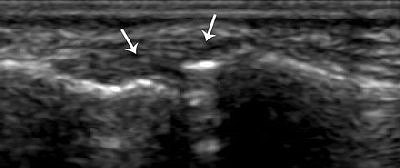

![]() |

| Strain of the radial collateral ligament. The left side of the images is distal. Above, coronal US scan of the thumb shows a thickened elongated radial collateral ligament (R). Below, coronal US scan of the contralateral thumb, obtained for comparison, shows a normal radial collateral ligament (arrows). "US Diagnosis of UCL Tears of the Thumb and Stener Lesions: Technique, Pattern-based Approach, and Differential Diagnosis," Ebrahim FS, et al. RadioGraphics 2006;26:1007-1020. |